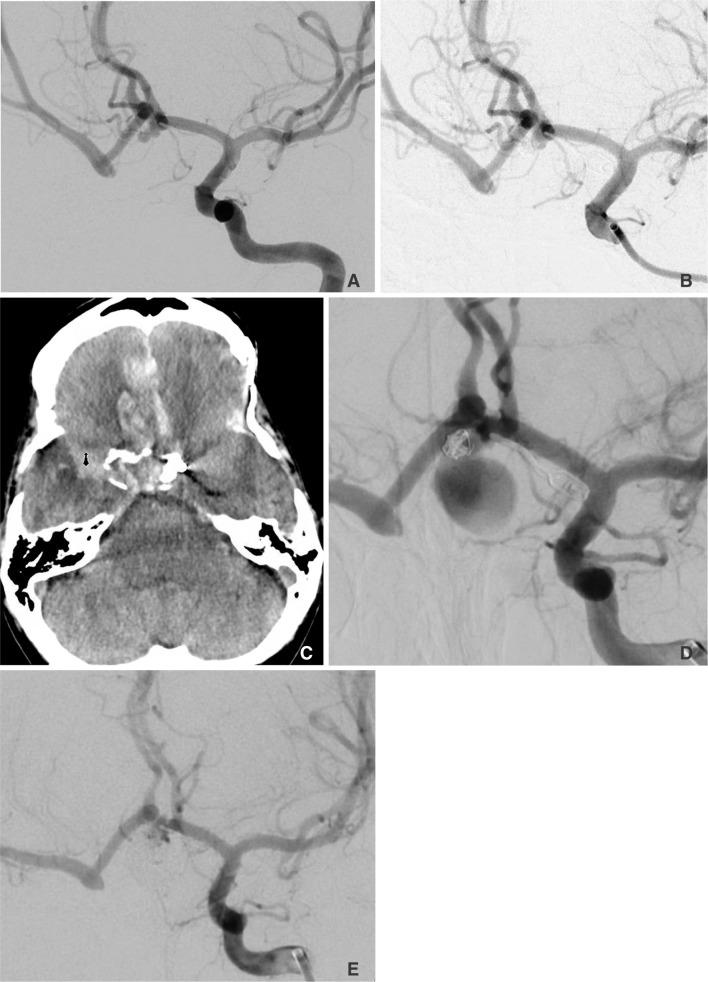

This case series and literature review serves to illustrate a relationship between spontaneous carotid occlusion and rapid enlargement of cerebral aneurysms.

In our case series, we demonstrated that increased hemodynamic stress on collateral vessels caused by a spontaneous carotid occlusion may contribute to unusually rapid aneurysm growth and/or rupture.

在我们的病例系列中,我们证明了自发性颈动脉闭塞引起的侧支血管血流动力学压力增加可能导致动脉瘤异常快速生长和/或破裂。